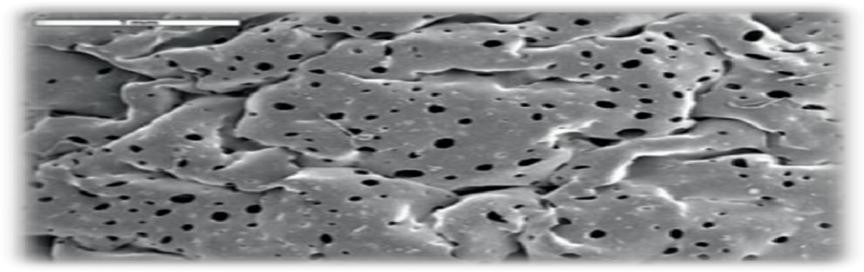

7) Morphological Analysis

7.1) Scanning electron microscopy

Scanning electron microscopy (SEM) experiments were conducted using the dried SPH to ascertain the dry samples' morphology.